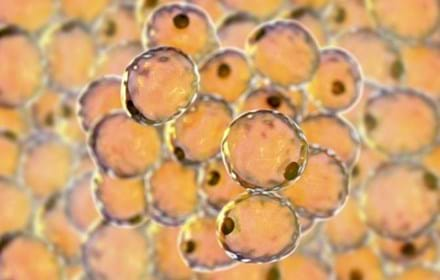

Kan cellterapi bota diabetes?

Proteinet som skyddar insulinproducerande celler

Försök att rädda kvarvarande insulinproduktion